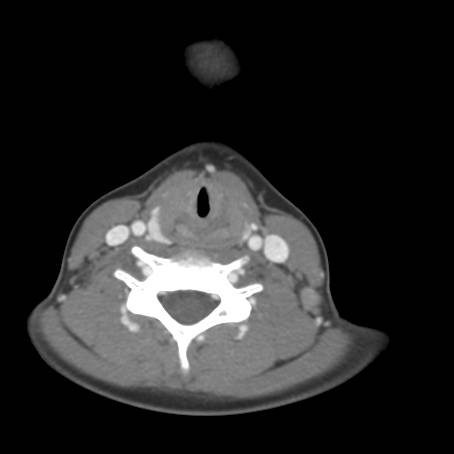

Fig.4a - normal epiglottis and arytenoids; Fig.4b - normal vocal cords, fullness seen below cords; Fig.4c - irregular mucosa in subglottic space with stenosis; Fig.4d-f - normal trachea below subglottic space with normal subsegmental bronchi (blood seen is iatrogenic related to procedure)

![]() Figure 5a |

![]() Figure 5b |

![]() Figure 5c |

Describe CT.